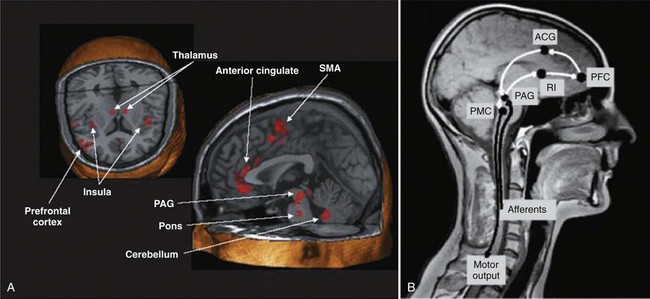

The micturition process can be visualized as a complex of neural circuits in the brain and spinal cord that coordinate the activity of smooth muscle in the bladder and urethra (Torrens and Morrison, 1987; de Groat et al, 1993a; Yoshimura and de Groat, 1997). These circuits act as on-off switches to alternate the lower urinary tract between two modes of operation: storage and elimination.

Injuries or diseases of the nervous system in adults can disrupt the voluntary control of micturition, causing the reemergence of reflex micturition and resulting in detrusor overactivity and urgency incontinence (Fig. 60–1) (Torrens and Morrison, 1987; Wein, 1992; de Groat et al, 1993a; Yoshimura and de Groat, 1997). Because of the complexity of the central nervous control of the lower urinary tract, urgency incontinence can result from a variety of neurologic disorders. In addition, urgency incontinence may be due to intrinsic detrusor myogenic abnormalities, resulting in detrusor overactivity (Brading, 1997b). The morphology and function of the detrusor wall are reviewed, including new insights into the urothelium.

The lower urinary tract is innervated by three sets of peripheral nerves involving the parasympathetic, sympathetic, and somatic nervous systems (Fig. 60–12). Pelvic parasympathetic nerves arise at the sacral level of the spinal cord, excite the bladder, and relax the urethra. Lumbar sympathetic nerves inhibit the bladder body and excite the bladder base and urethra. Pudendal nerves excite the external urethral sphincter. These nerves contain afferent (sensory) as well as efferent axons (Wein, 1992; de Groat et al, 1993a; Sugaya et al, 1997; Yoshimura et al, 2008).